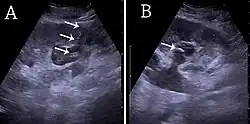

- ^ Content initially copied from: Hansen KL, Nielsen MB, Ewertsen C (December 2015). "Ultrasonography of the Kidney: A Pictorial Review". Diagnostics. 6 (1): 2. doi:10.3390/diagnostics6010002. PMC 4808817. PMID 26838799. (CC-BY 4.0)